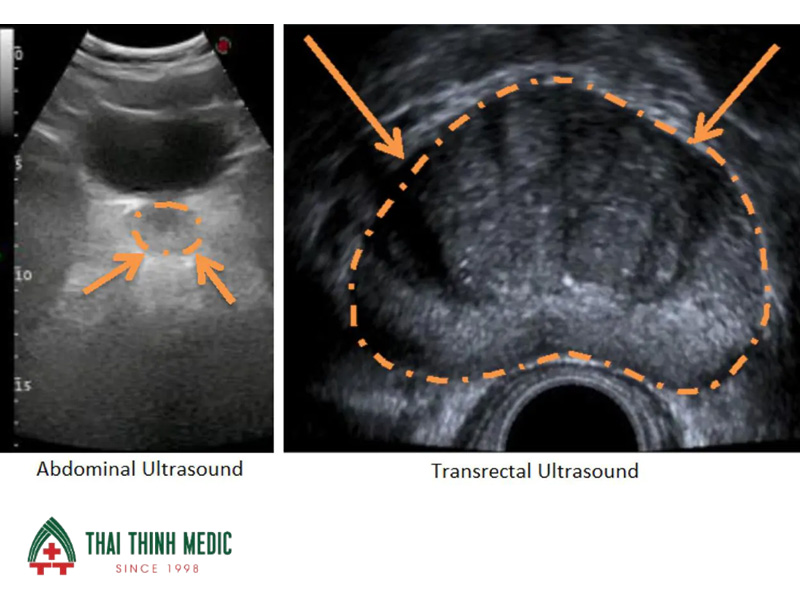

Sự phát triển của công nghệ hình ảnh đã giúp các bác sĩ quan sát cấu trúc bên trong của tuyến tiền liệt một cách chi tiết nhất. Siêu âm tuyến tiền liệt là phương pháp phổ biến nhất để đo chính xác kích thước, thể tích tuyến và kiểm tra các dấu hiệu viêm nhiễm hoặc vôi hóa. Hình ảnh siêu âm cũng hỗ trợ đắc lực trong việc hướng dẫn kim sinh thiết đi đúng vào vị trí có tổn thương nghi ngờ.

Hình ảnh trên siêu âm